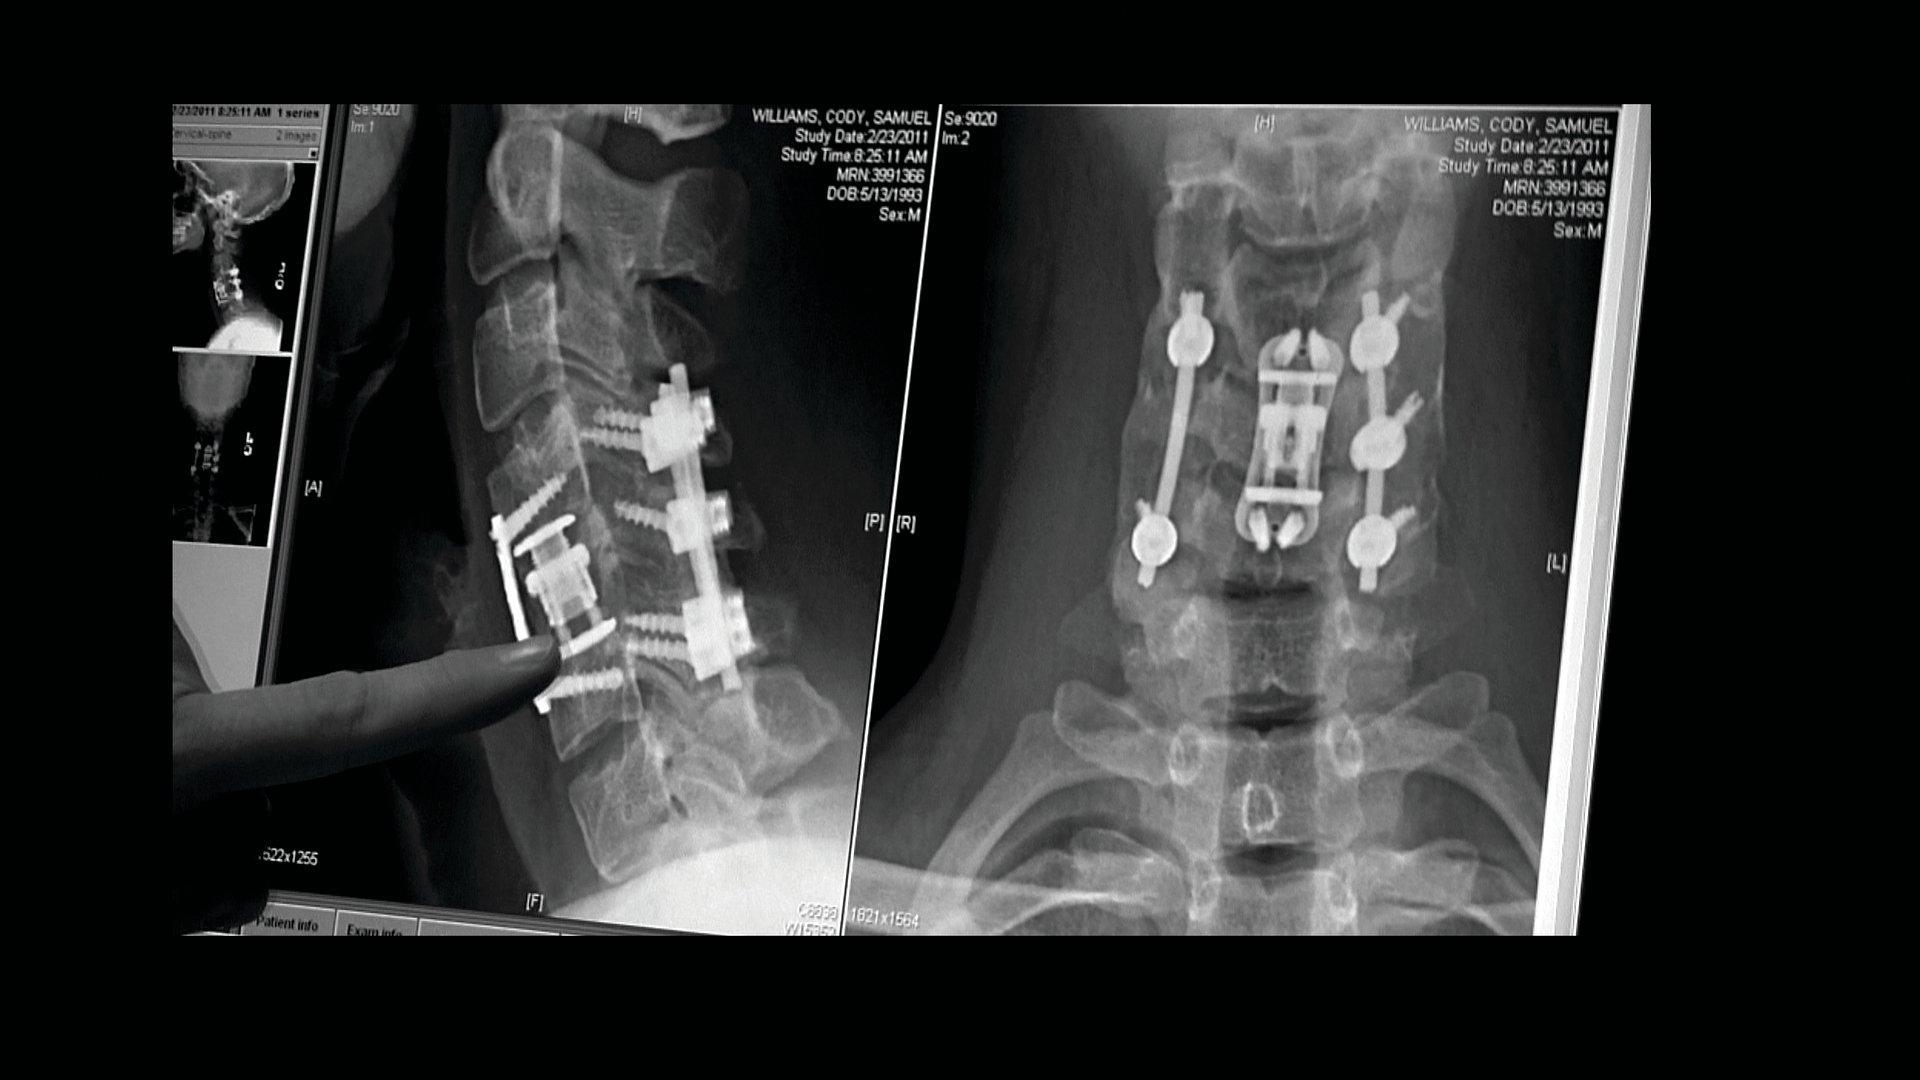

Cody Williams